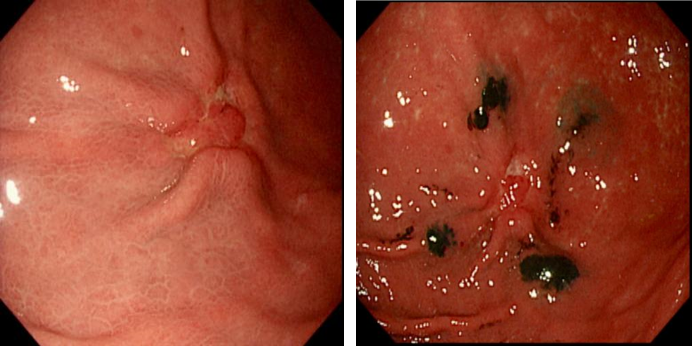

为更精准地切除胃部病灶,胃肠外科顾佳毅医生在术前为患者进行了胃镜下病灶纳米碳定位术。这一技术利用黑色的纳米碳粒子对病灶进行定位,使医生在术中能直观地观察并切除病变组织,保留更多健康组织,减少手术创伤,提高手术的精准度和安全性。

左图胃镜(定位前)、 右图胃镜(定位后)